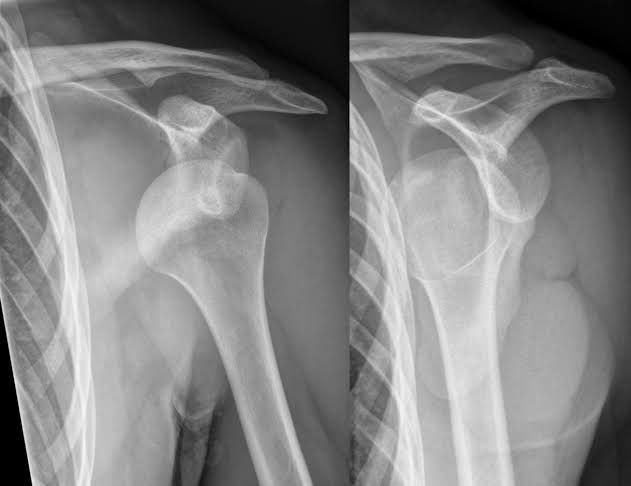

A dislocated shoulder is an injury in which your upper arm bone pops out of the cup-shaped socket that's part of your shoulder blade. The shoulder is the body's most mobile joint, which makes it susceptible to dislocation. If you suspect a dislocated shoulder, seek prompt medical attention.